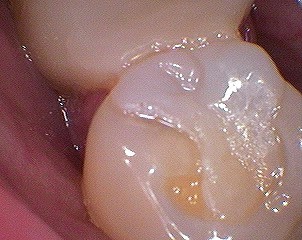

D'autres photos:

Patient 8 qsxfa6 - Eugenol

Patient 9 kmkpcy - Eugenol

Patient 1 naxbfx - Eugenol

Patient 10 osyvpe - Eugenol

et retouchées:

Patient 8 dhkiyd - Eugenol

Patient 9 rlzvzy - Eugenol

Patient 1 w3prxq - Eugenol

Patient 10 athrpl - Eugenol